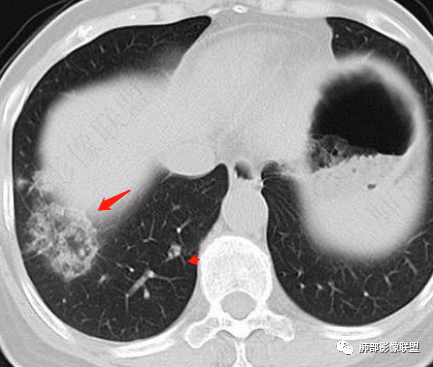

2、CT表现为两肺下叶结节影、斑片影、磨玻璃影,沿支气管血管束分布,部分支气管壁显示增厚。粗略一看部分病灶内似可见“细网格影”,但是仔细观察,可发现此“细网格影”不同于我们常见的“细网格影”,尤其是右肺下叶病灶,可以观察到病灶内部的网格上有高密度结节感或颗粒感,部分层面见“反晕征”,且反晕的边缘亦可观察到结节感。未见胸腔积液。

3、反晕征又称为环礁征、环岛征或环状珊瑚岛征,表现为中心磨玻璃影,周围为高密度影环绕,最初被认为是隐源性机化性肺炎(COP)的特征性表现之一,但随后不断有研究发现反晕征亦可出现在多种感染及非感染性疾病、肿瘤及非肿瘤性疾病中。反晕征的常见疾病谱有:①感染性疾病:肺孢子菌病、侵袭性肺真菌感染、肺结核、病毒性肺炎;②非感染性疾病:肺淋巴瘤样肉芽肿、韦格氏肉芽肿、 结节病、机化性肺炎(包括隐源性和继发性)、肺栓塞;③肺腺癌以及肺肿瘤治疗后。

4、本例急性病程,发热、咳嗽,结合影像多发磨玻璃影表现首先会考虑到感染性病变:①病毒性肺炎,病灶间质分布为主,常较弥漫,外围多见,临床症状重且常与影像表现同步;②支原体肺炎,病变多为1-2叶段、少数多叶段分布,支气管壁弥漫较均匀增厚,可见树芽征、腺泡结节及树雾征;③肺结核,上叶尖后段及下叶背段多见,多灶性、多态性,树芽征,可有空洞、钙化等;④机化性肺炎,病变胸膜下和支气管血管束分布,可有实变、结节及反晕征。

本例病变以两肺下叶为主,非结核好发部位,通常会想到感染性病变,右肺下叶病灶高密度结节感、反晕征,较为符合继发性肺结核(间质浸润为主),但双肺散落的相对柔和淡薄小片影给诊断带来困惑。

2、好发部位与其它结核类似,上叶及下叶背段为主。 3、烟花征,反晕征,环呈结节状,可以伴随空洞,树芽征,结节灶,胸水。(反晕征:一般周围实性环形高密度影,中央呈低密度;一般环超过圆的3/4,结核的环主要是小叶核心结节组成,类似于多发树芽征聚集,边缘结节感。中央的晕:可以是腺泡结节,树芽征,细网状,磨玻璃影,很少正常,主要成分是小叶内间质增厚、小叶核心结节、肺泡内病变。)其实也体现了结核的多灶性、多态性特点。